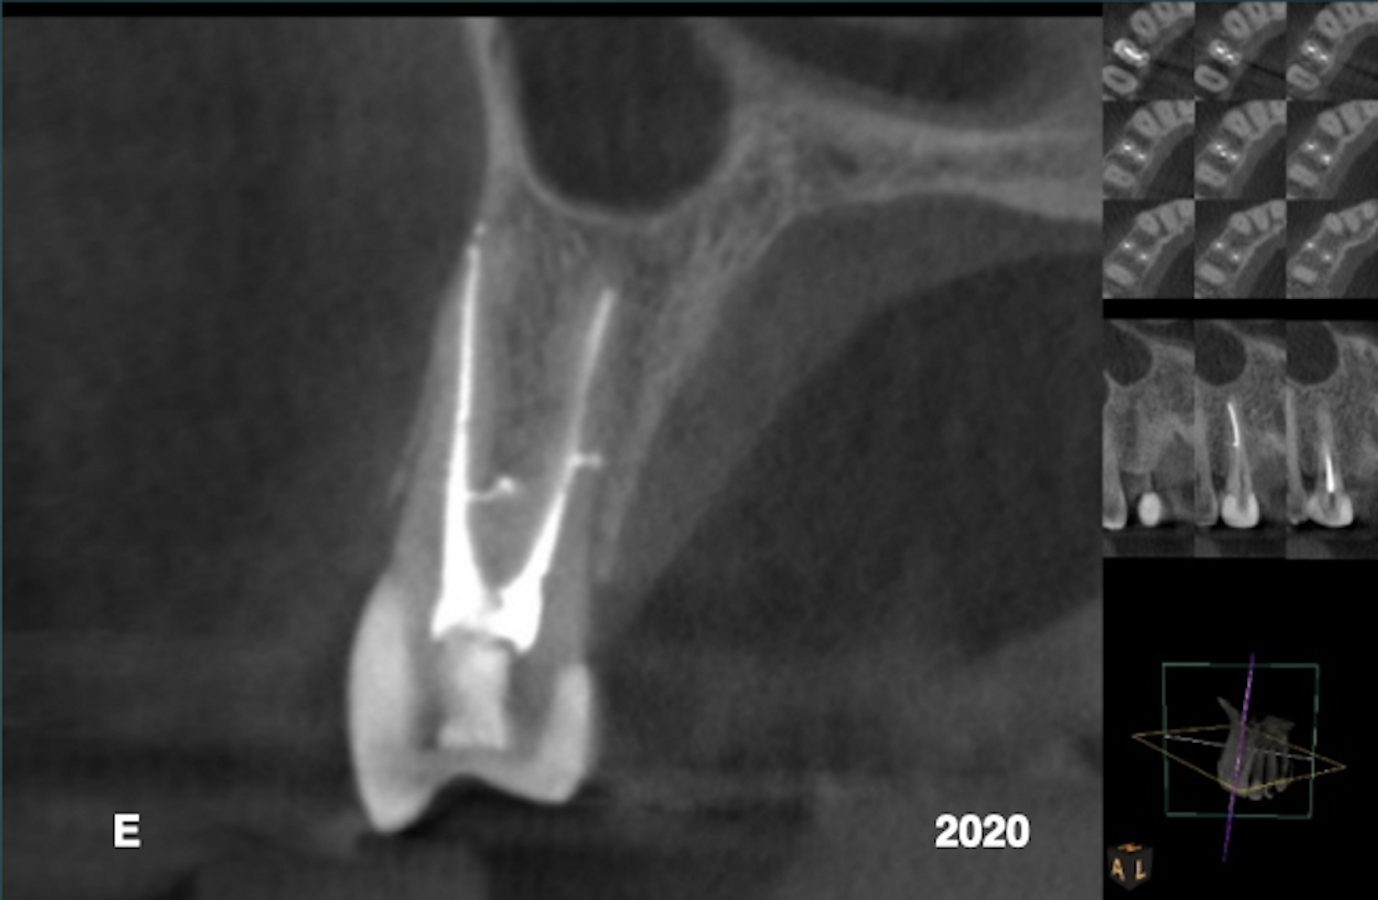

En octobre 2015, un patient de sexe masculin de 55 ans, précédemment vu pour un traitement au cabinet, s'est auto-référé pour un deuxième avis concernant l'extraction recommandée d'une dent suspectée fracturée dans le quadrant maxillaire droit. Il a signalé qu'un léger gonflement était devenu apparent au cours de la semaine dernière. L'examen clinique a noté un gonflement fluctuant entre la dent n ° 15 et la dent n ° 14, et un défaut de sondage de 12 mm a été détecté le long de l'angle de la ligne mésiobuccale de la dent n ° 15.

Le patient a fourni une radiographie périapicale montrant une radioclarté périradiculaire mésio-proximale associée à la dent #15 (Fig. 1). La coupe sagittale du volume CBCT (Carestream CS 9000, Carestream Dental) montrait l'étendue de la lésion (Fig. 2). Dans la précédente thérapie radiculaire, seul le canal buccal avait été détecté et traité. La coupe axiale montrait un canal palatin non traité (Fig. 3) . Un tenon fibré placé dans le canal buccal avait été utilisé pour retenir le noyau. Le patient a été informé que la broche d'ancrage mal orientée s'étendait dans le ligament parodontal. Avec l'accord du patient, il a été décidé de traiter sélectivement le canal palatin.

Après une période intermédiaire de traitement à l'hydroxyde de calcium de six semaines (UltraCal XS, Ultradent ; Figs. 4 & 5), 6 l'espace canalaire a été obturé à l'aide d'une technique de condensation verticale chaude. 7 Le matériel d'obturation a été exprimé dans une porte de sortie ramifiée latérale (Fig. 6). Le suivi de quatre ans a montré une résolution de la lésion latérale (Figs. 7–9). La présomption initiale d'une racine fracturée s'est avérée fausse, ce qui suggère que le diagnostic d'affections basé sur une acquisition de données insuffisante n'est pas fiable. L'utilisation du CBCT est un impératif dans les procédures endodontiques de toute nature, à condition que les principes ALARA (aussi bas que raisonnablement réalisable) concernant la dose de rayonnement soient suivis.

Cas 1—Fig. 1 : Une zone de raréfaction périradiculaire était évidente le long de la face mésio-proximale de la dent #15. Un traitement antérieur du canal radiculaire et un tenon et un noyau retenus par une broche supportant une couronne en zircone ont été notés. Fig. 2 : La coupe sagittale du volume CBCT montrait la lésion latérale s'étendant jusqu'à la crête alvéolaire. Fig. 3 : La coupe axiale du volume CBCT montre l'étendue de la raréfaction adjacente à la face mésiale de la racine et la présence d'un canal palatin non traité. Fig. 4 : Un traitement sélectif du canal palatin a été réalisé. De l'hydroxyde de calcium a été inséré dans l'espace canalaire. Fig. 5 : L'extrusion du médicament provisoire à base d'hydroxyde de calcium à travers la zone sulculaire de la dent n° 15 était évidente. Fig. 6 : Une branche latérale de l'espace canalaire contenant le matériau d'obturation sortait dans l'interface des tiers moyen et apical de la racine. Fig. 7 : Une radiographie périapicale prise quatre ans après le traitement a montré une régénération osseuse et la reformation du ligament parodontal. Fig. 8 : La coupe coronale du volume CBCT montrait la radiotransparence périradiculaire préopératoire. Fig. 9 : La coupe coronale du volume CBCT prise quatre ans après le traitement a montré la résolution de la radiotransparence périradiculaire.